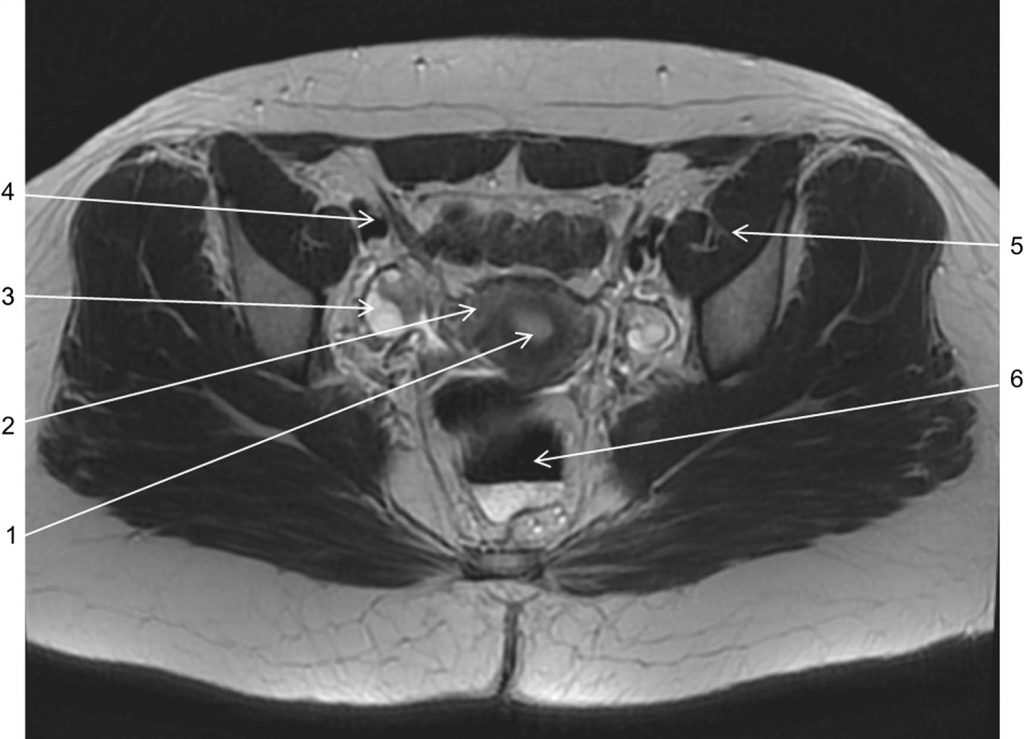

Fig. 19.1. Coupe IRM dans le plan axial en pondération T2 passant au niveau du toit des cotyles.

1. Endomètre. 2. Myomètre. 3. Ovaire droit. 4. Vaisseaux iliaques externes. 5. Muscle obturateur. 6. Rectum.

Source : CERF, CNEBMN, 2022.